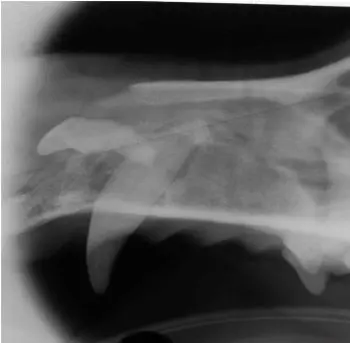

Figure 2. Right maxilla, showing the roots of the upper fourth premolar (#108) located just ventral to the infraorbital canal (arrow).